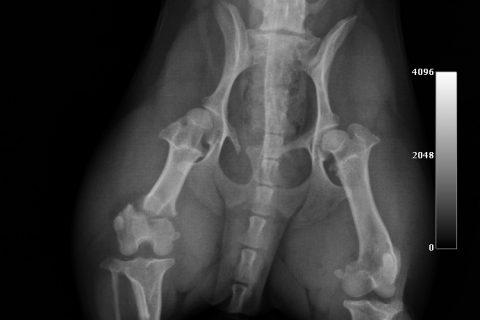

症例:大腿骨先端の骨折

今回は、大腿骨の先端が骨折した症状です。

専門的には、大腿骨遠位端骨折といいます。

この骨折は比較的珍しい骨折ですが、今回は滑車溝の真ん中で骨折した非常に珍しい骨折です。

大腿骨遠位端骨折は、比較的手術が難しい骨折です。当院では院内で矢状ピンを作成して手術しています。